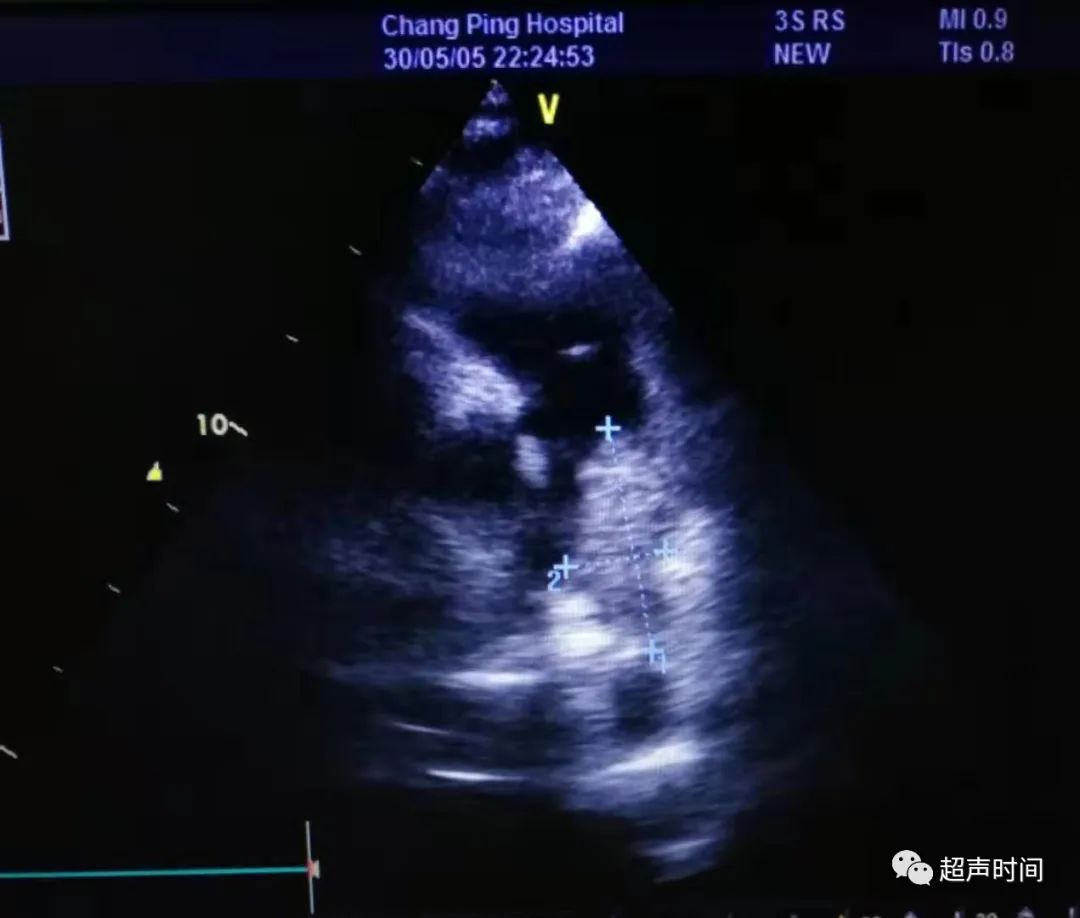

急诊床旁心脏超声所见如下:

图 1 和图 2 左室长轴切面示右室显著增大,其前壁运动减弱、消失,室间隔呈矛盾运动,左室收缩功能正常

此时,根据超声所见并结合临床,考虑可能存在肺栓塞。于是再回去仔细检查大动脉短轴切面,果不其然: